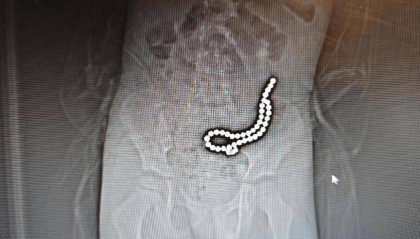

整整37颗!云南4岁孩子身体里取出……医生紧急提醒!

磁力珠色彩绚丽、玩法多样,深受小朋友喜爱。但如果误食,后果却会很严重。 近日,丽江市人民医院接收了一...